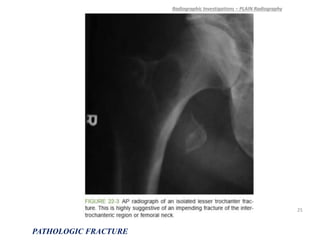

• 24.

An isolated avulsionof the lesser trochanter is almost always pathologic, and this specific injury should arouse suspicion of occult metastatic disease or lymphoma and an imminent femoral neck fracture. A cortical lesion in an adult is usually a metastasis, most commonly from lung cancer. Radiographic Investigations – PLAIN Radiography PATHOLOGIC FRACTURE 24

• 25.

Radiographic Investigations –PLAIN Radiography PATHOLOGIC FRACTURE 25